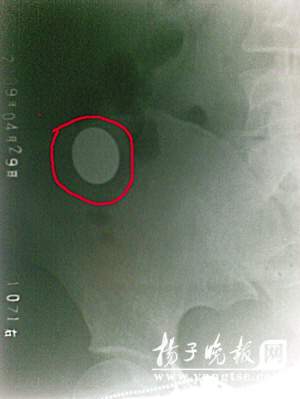

經(jīng)X光片檢查,何小姐腹中有一枚一元硬幣,幸運的是它已穿過消化道最狹窄的胃幽門進入大腸,如不出意外,過幾個小時,就可排出體外。外科的孫主任說,金屬異物進入腸道被蠕動和摩擦,極有可能發(fā)生腸穿孔和出血,最好及時就診。就此事,記者采訪了江蘇省雜技家協(xié)會理事、魔術(shù)俱樂部主任方振勇。他說,魔術(shù)“吞硬幣”是簡單的小魔術(shù),它重在手法和手技,魔術(shù)師將硬幣放入口中只是個假動作,然后將硬幣從別的地方拿出來,對于初學(xué)者,如果沒有掌握要領(lǐng),不要輕易自創(chuàng)和模仿。(任國勇)